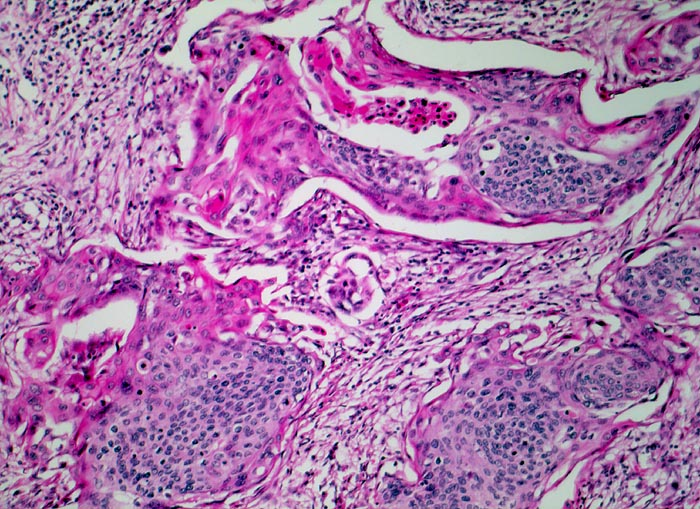

PathoPic – image database / PathoPic ID 4583 - Invasives Plattenepithelkarzinom der Zervix

Invasives Plattenepithelkarzinom der Zervix

Unregelmässig begrenzte Tumorzellstränge liegen in einem lockeren desmoplastischen Tumorstroma. Ein Teil der Tumorzellen zeigt eine deutliche plattenepitheliale Differenzierung mit reichlich hypereosinophilem Zytoplasma.

Im Portioabstrich anlässlich einer gynäkologischen Kontrolle Pap V, Hysterektomie

Histologie

100